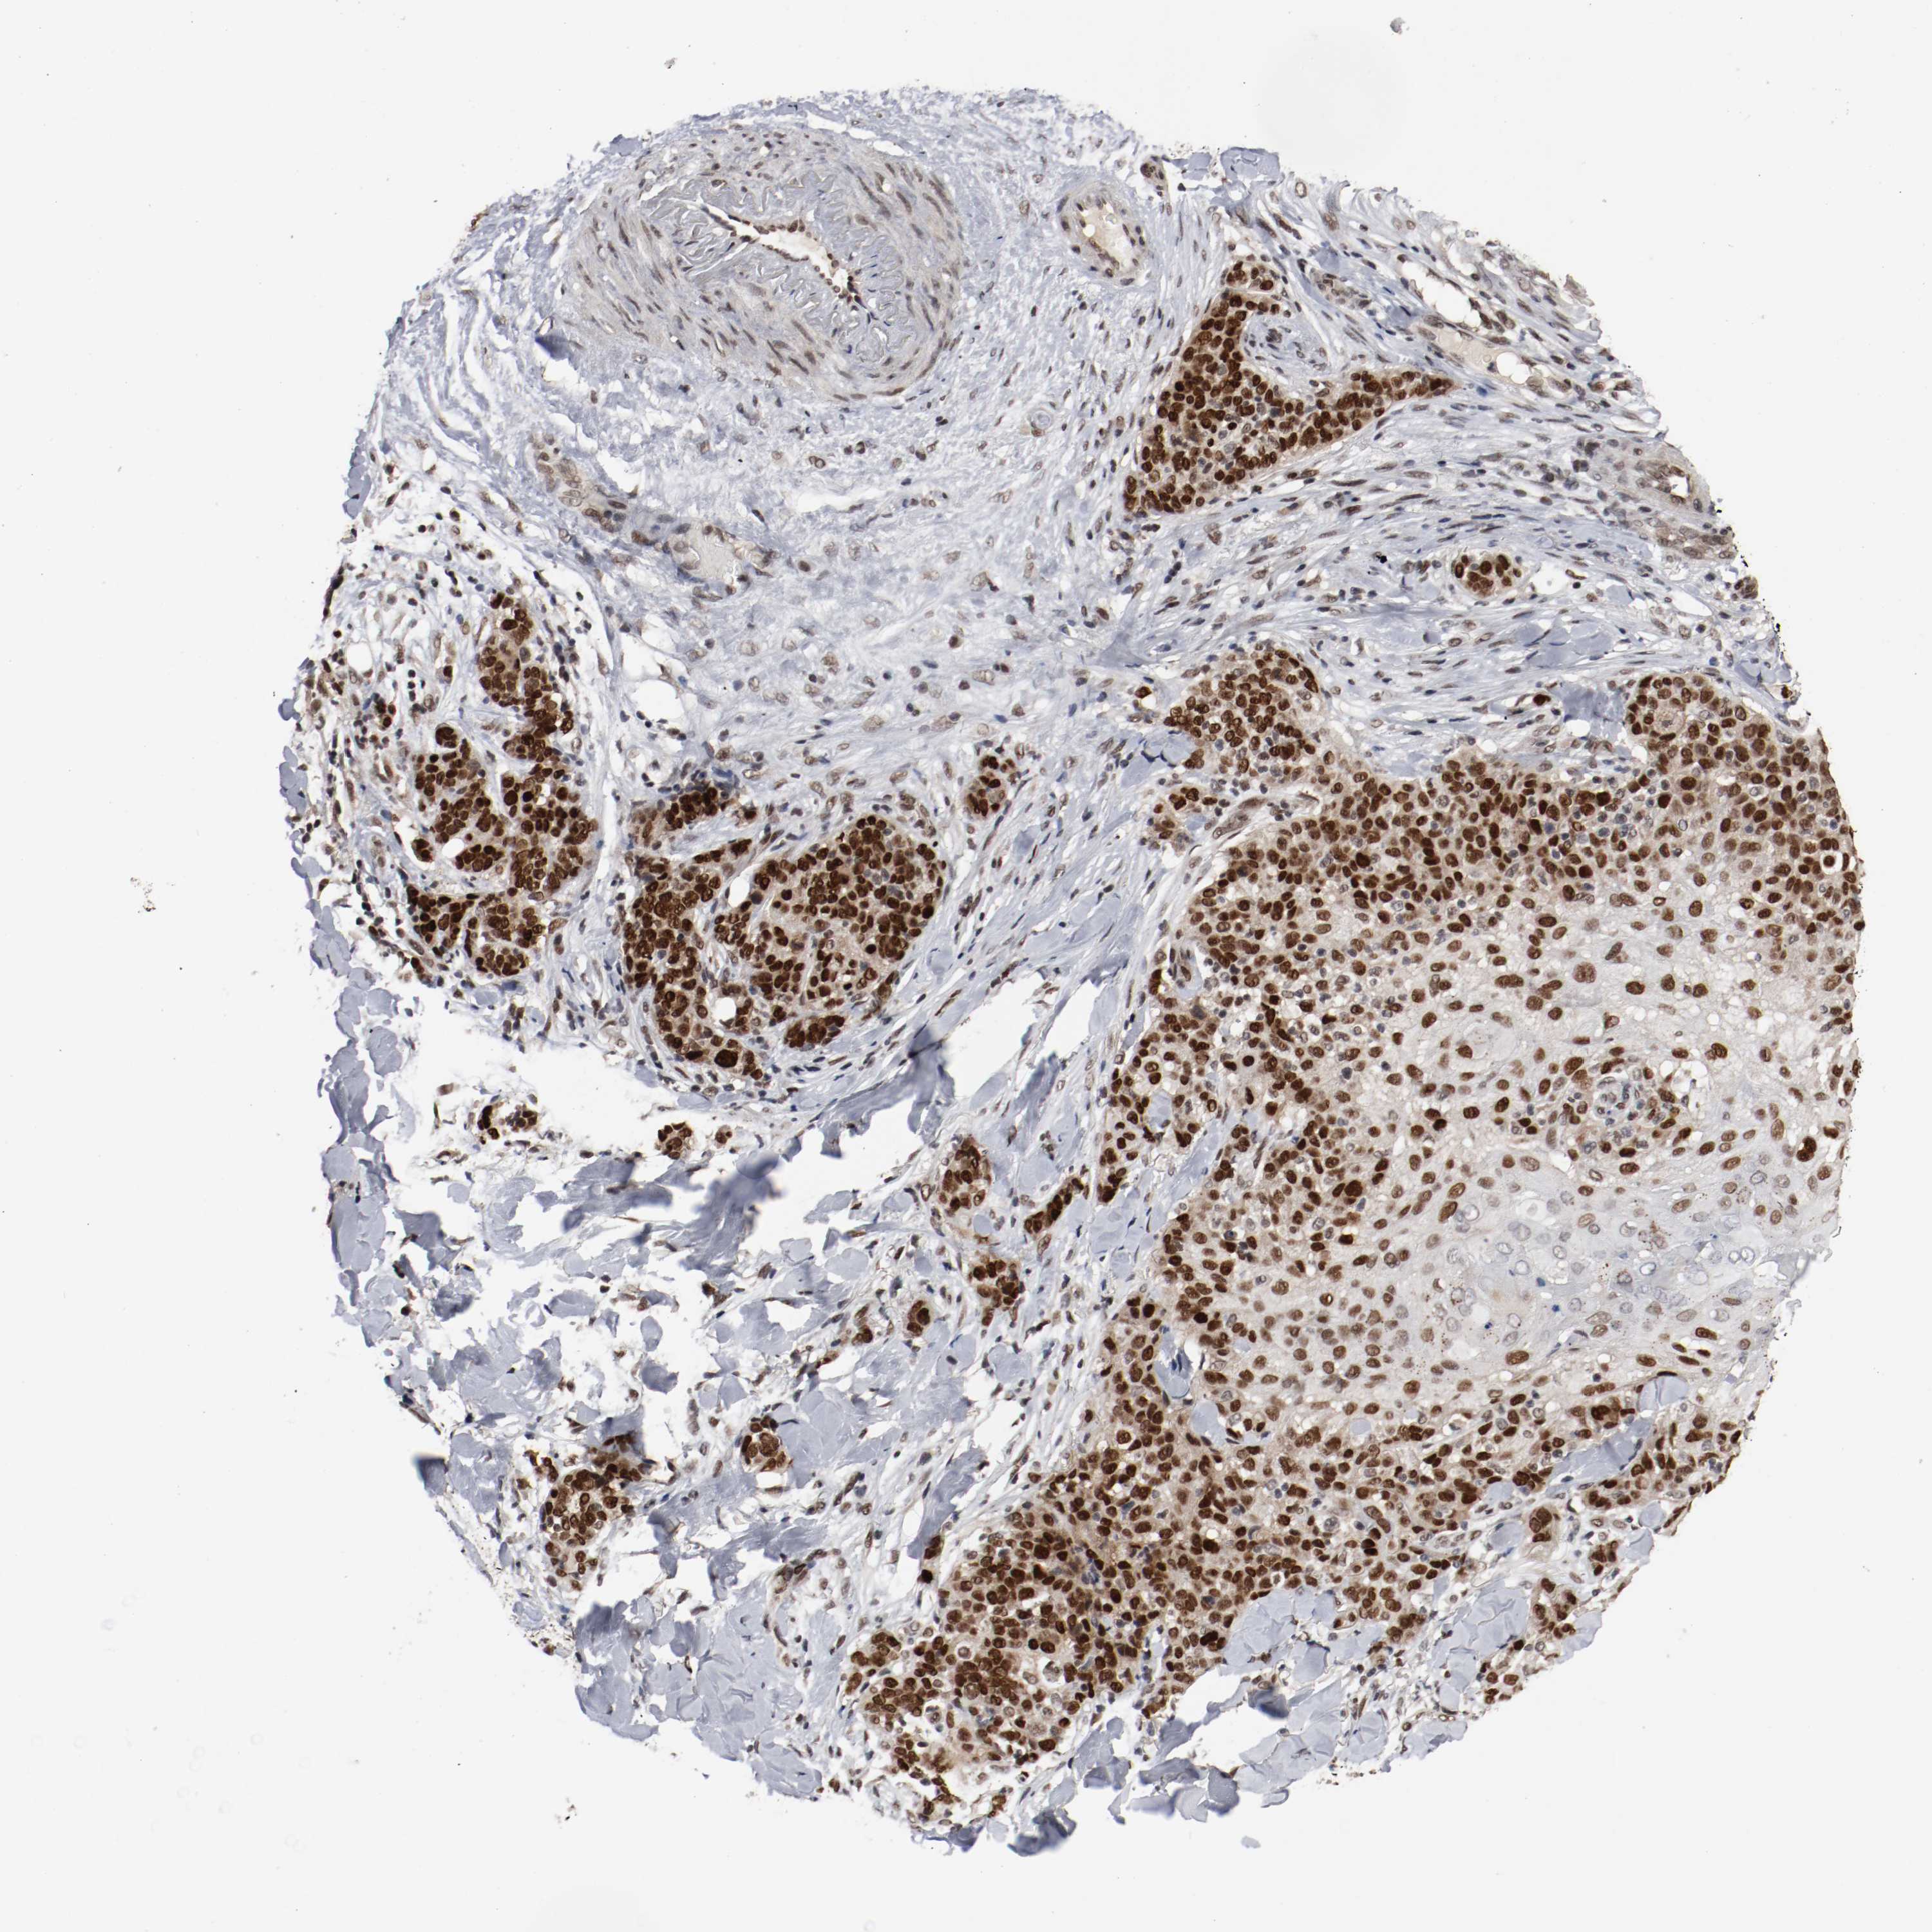

SKIN CANCER - Protein expressioni

A mouse-over function shows sample information and annotation data. Click on an image to view it in a full screen mode. Samples can be filtered based on level of antibody staining by selecting one or several of the following categories: high, medium, low and not detected. The assay and annotation is described here.

Each image is clickable and will lead to virtual microscopy that enables deeper exploration of all samples and also displays staining intensity scores, fraction scores and subcellular localization as well as patient and tissue information for each sample.

Antibody HPA004794

Staining

High

Intensity

Strong

Quantity

>75%

Location

Nuclear

Squamous cell carcinoma, NOS

Basal cell carcinoma